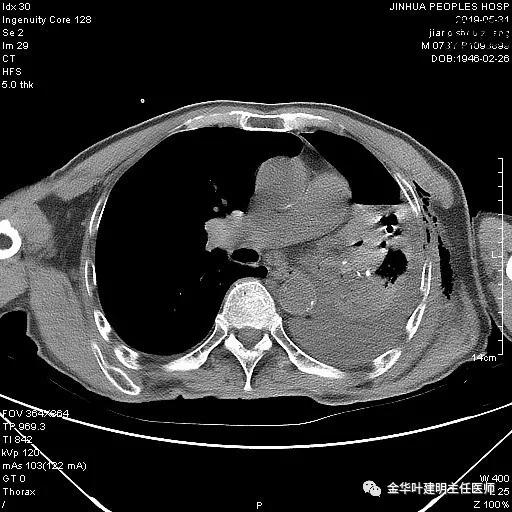

以上是肺窗表现,下面为纵隔窗影像:

因为引流出的胸液为血性,但感觉不是特别鲜,查血色素9.5 g/L,术前是12.7g/L。当时考虑胸腔内出血可能,较为纠结的是是否需要进胸探查。但鉴于血压正常、心率不快,一般情况良好,不似胸内大出血休克的表现,所以仍想继续视察保守治疗。